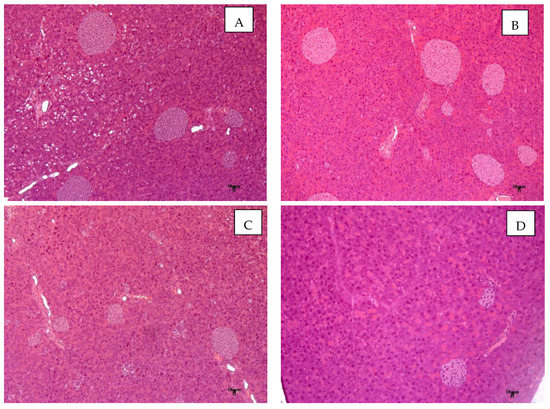

Histological examination revealed fatty hepatosis (Figure 8B) and pronounced hyperplasia of islet apparatus in the endocrine part of the pancreas (Figure 9B) in AY mice. Brown adipose tissue examination revealed a marked increase in the adipocyte fat content and fat cysts formed from large fat droplets could be found (Figure 10B). The adipocyte size was also dramatically increased in the white adipose tissue (Figure 11B). These metabolic abnormalities were improved in mice treated with metformin (Figure 8C, Figure 9C, Figure 10C and Figure 11C).

Figure 8.

Histological evaluation of the liver in mice after 4 weeks of experiment. (A) AY mice treated by compound 9a at a dose of 30 mg/kg, (B) AY mice (untreated), (C) AY mice treated by metformin at a dose of 250 mg/kg, (D) C57Bl/6 (healthy control). Hematoxylin and eosin staining, magnification ×200.

In animals treated with 9a, the morphological picture in the studied organs practically corresponds to that in the group of intact animals. Architectonics of the liver and pancreas had typical structure, and no pronounced infiltrative-necrotic, hemodynamic changes were found (Figure 8A and Figure 9A). In brown and white adipose tissue, the fat content in adipocytes was comparable with the intact group (Figure 10A and Figure 11A).